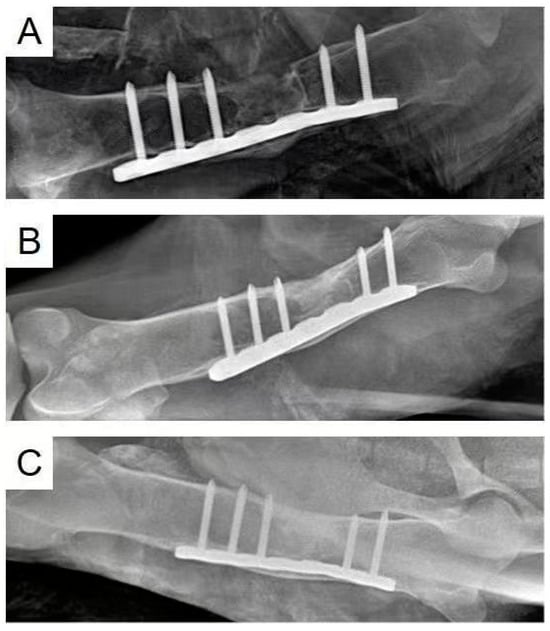

3.4. In Vivo Animal Experiments